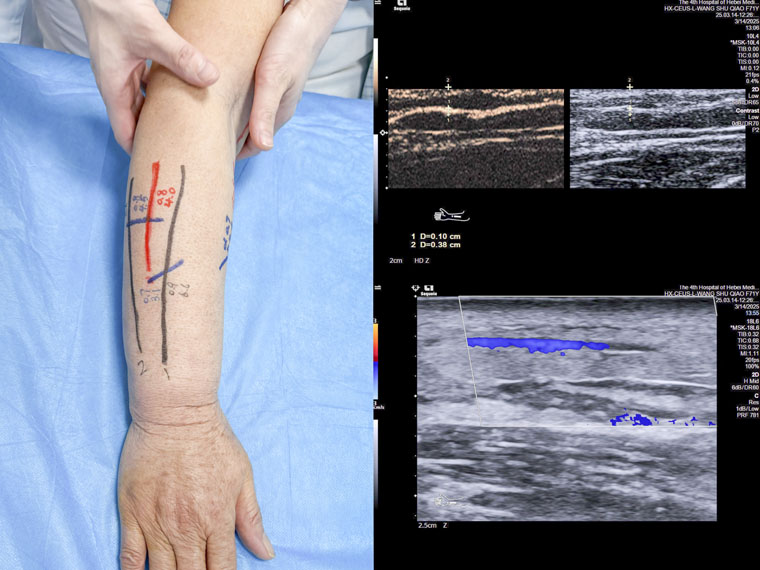

淋巴水肿患者术前定位的体表标记和超声造影的图像

在本次操作中,我院超声科殷兆麟主治医师协同科室负责人纪晓惠主任医师为一名乳腺癌术后淋巴水肿患者进行上肢淋巴管超声造影,诊断并评估淋巴管功能,精准识别有手术意义的皮下淋巴管及其邻近微静脉,并进行体表定位,助力我院乳腺中心完成河北省首例超声造影辅助下的淋巴管静脉吻合术。